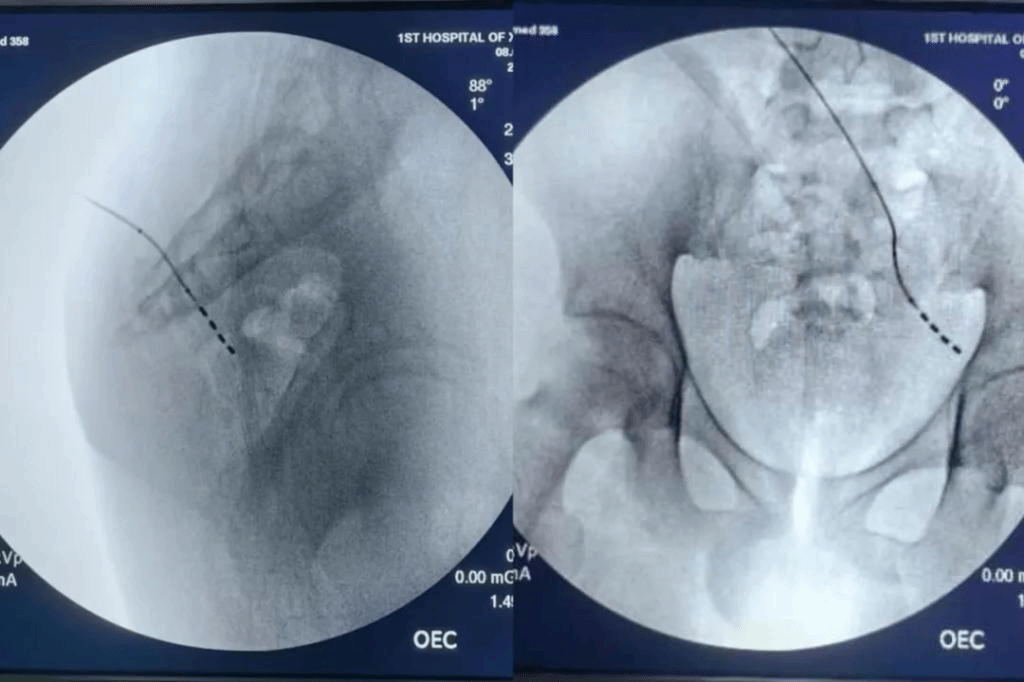

术中定位测试X片